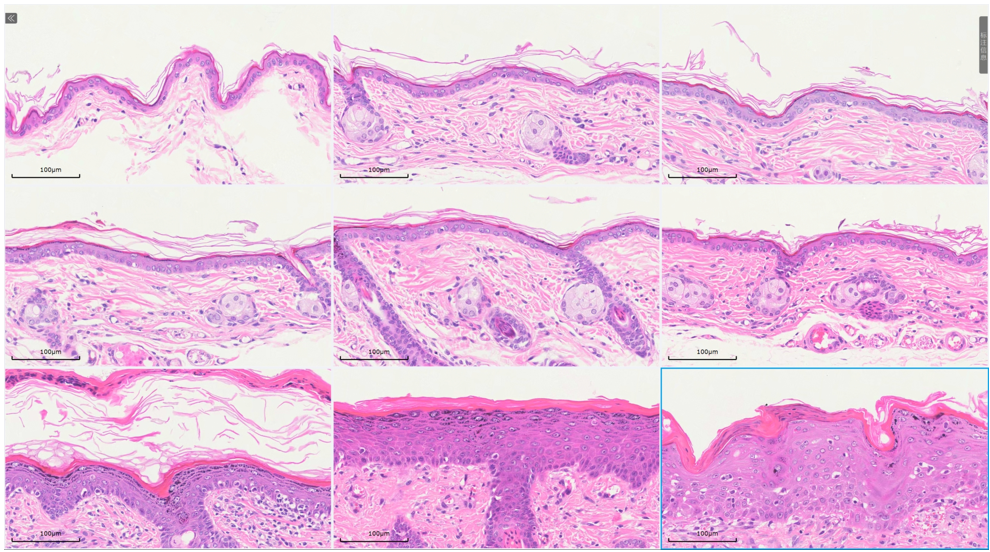

组织病理学

病理表现:经过OXA诱导后,可明显观察到的小鼠背部皮肤和右耳变厚,结痂。

通过测量数据分析,模型组背部皮肤的厚度在对照组的3倍左右,右耳皮肤最厚处是对照组的5倍左右。